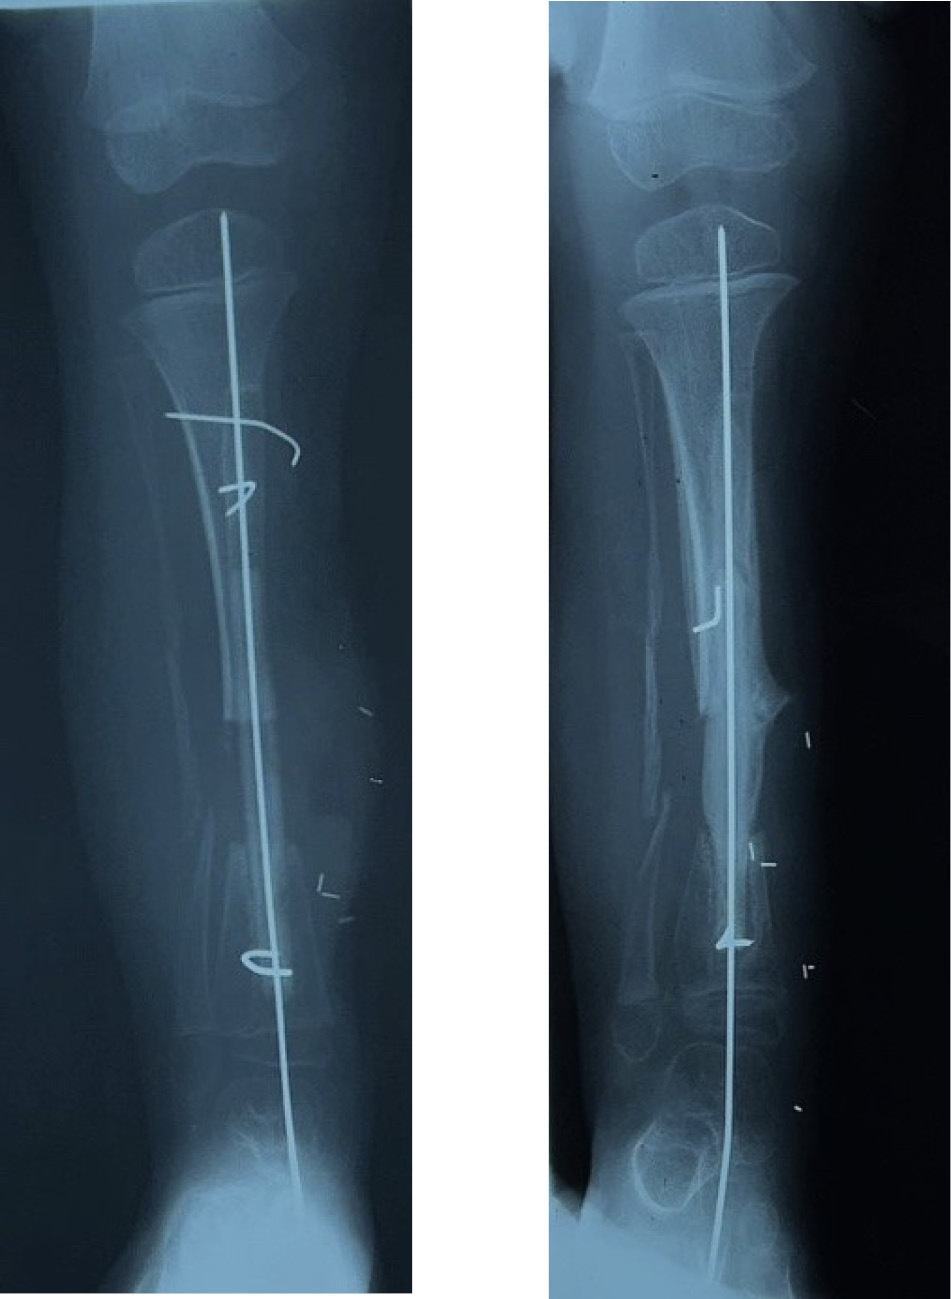

An 18 cm length of fibula was detached and transferred to bridge the 15 cm defect in the tibia. Periosteum was stripped from the distal end, dowelled into the tibia and secured with a screw. The proximal end was abutted against the underside of the growth plate of the tibia, balanced like a saucer on the end of a pole, and stabilised with an external fixateur (Figure 11A).

At three months the distal end of the fibula graft had united to the tibia. The fixateur was removed leaving behind the transfixing pins that were fixed into an above-knee plaster cast. At eight months the cast was removed, the limb placed in a caliper and weight bearing commenced. Union was noted at the upper end (Figure 11B). By two years dramatic hypertrophy of the transplanted fibula was noted together with growth from the proximal epiphysis (Figure 11C). The limbs had almost identical length (Figure 12), the knee and ankle joints were normal and the only disability was temporary weakness of the EDL in the donor leg.

The same applies in the tibia, where the fibula is placed always within the medullary cavity of the bone. There it has been maintained again with the external fixateur or simply an above-knee plaster cast. Notably hypertrophy is frequently initiated by an undisplaced, often unidentified stress fracture as shown in Cases 1, 9, 10 and 11 (Figures 5, 30 and 31). If a specific fixateur is unavailable, in an emergency several transverse pins, a bit of bone cement and any nearby long metal rod or stick will do!

Another form of fixation is an intramedullary nail or rod used in two of our nine cases of resection of a pseudarthrosis of the tibia in a child shown in Cases 12 and 13 (Figures 32 and 33). In these two cases, the distal tibial fragment could not be fixed to the fibula with a screw. Instead a Rush nail was passed from below through the heel, calcaneum, talus and distal tibia and into the medullary cavity of the transplanted fibula. The result was exactly the same as the other seven cases. Even in plaster you can’t keep a child still! By six weeks all, including the two with nails, showed union and early bone hypertrophy (Figures 32 and 33).